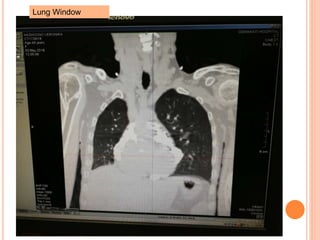

Lung Window

NOT MS. XX